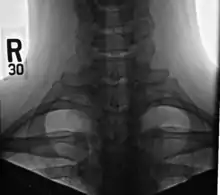

Cervical rib

A cervical rib in humans is an extra rib which arises from the seventh cervical vertebra. Their presence is a congenital abnormality located above the normal first rib. A cervical rib is estimated to occur in 0.2%[2] to 0.5%[3] (1 in 200 to 500) of the population.[4] People may have a cervical rib on the right, left or both sides.[5][6]

Diagnosis

On imaging, cervical ribs can be distinguished because their transverse processes are directed inferolaterally, whereas those of the adjacent thoracic spine are directed anterolaterally.[11]